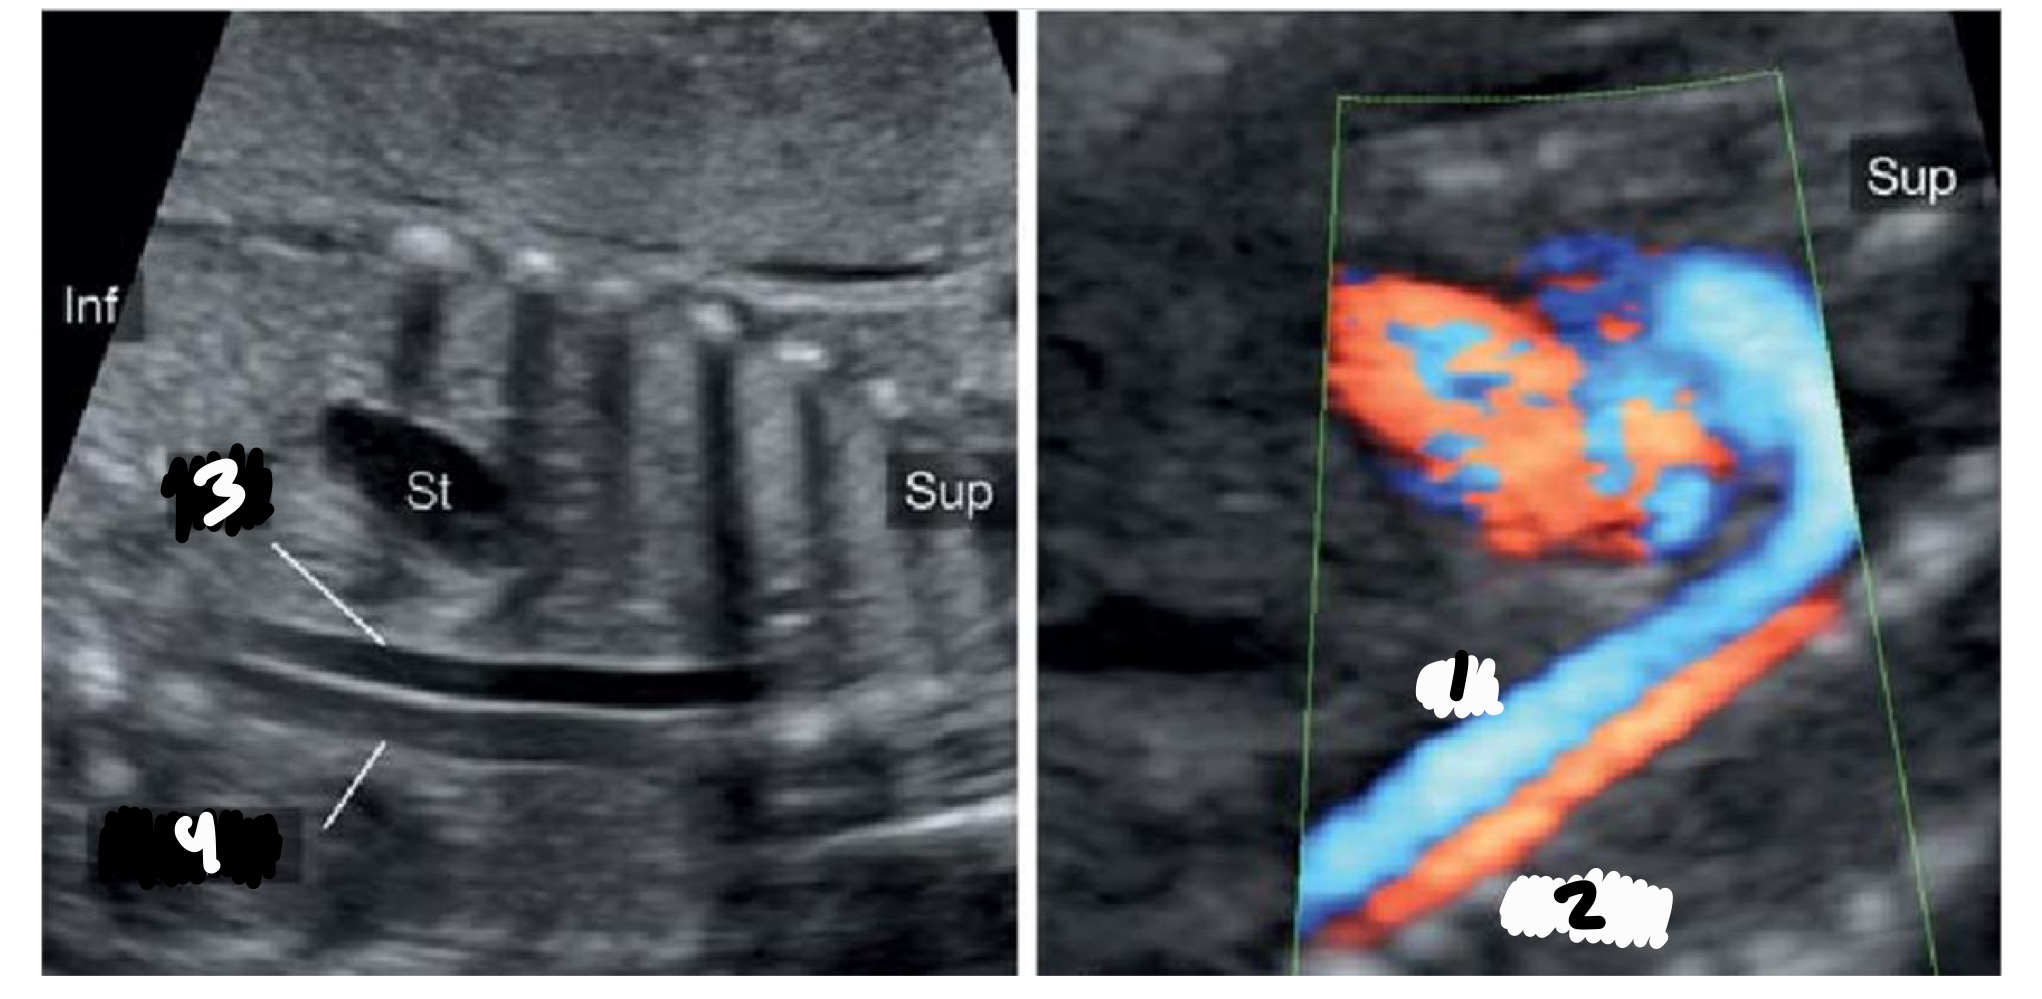

What is the shape of the aortic arch

Candy cane (tight curve)

What branches arise from the aortic arch IN ORDER

Brachiocephalic, left common carotid, left subclavian

Ascending aorta

Innominate/brachiocephalic artery

Left common carotid

Left subclavian artery

Isthmus

Descending AO

What is the shape of the ductal arch

Hockey stick (wide curve)

How many branches does the ductal arch have

None

Right ventricle

Pulmonary artery

Ductus arteriosis

Descending aorta

What vessels are seen in the 3 vessel view

SVC, aorta, pulmonary artery

Which vessel is smallest in 3VV

SVC

Which vessel is largest in 3VV

How should the pulmonary artery compare to the aorta

Equal or larger

Aorta

Trachea

Azygous

What structure connects the aorta and pulmonary artery in 3VTV

Ductus arteriosus

Where is the trachea located relative to the aorta

To the right

What direction should flow be in 3VTV

Away from the transducer